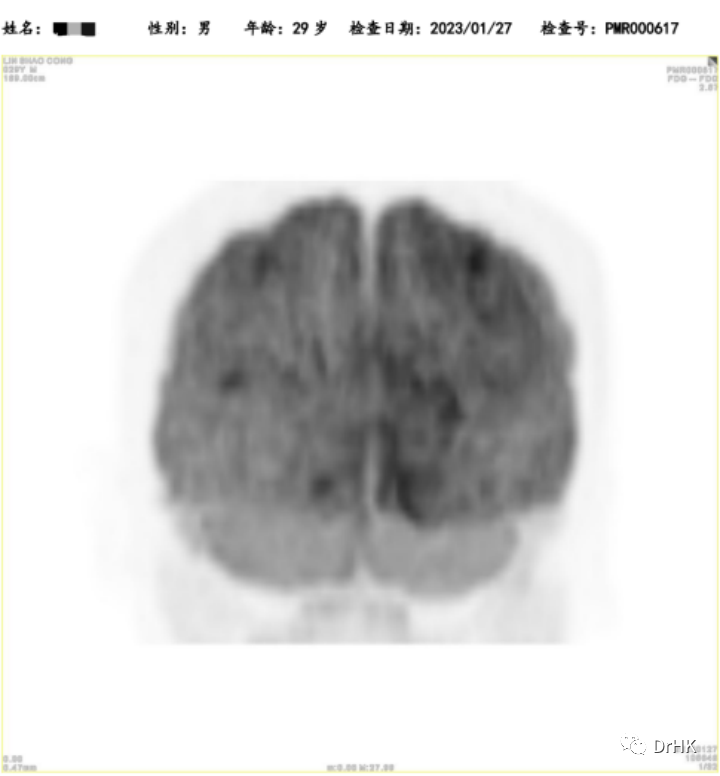

PET-CT:Deauville 评分 5 分。(1) 肝脏累及,大小约 3.2*2.6*3.7 cm,最大 SUV 值 22.4; (2) 脑部:右侧颞叶深部、基底节区稍低密度灶,结合 MRI 图像,考虑淋巴瘤累及;(3) 全身多发骨(双侧肩胛骨、锁骨、肋骨、胸骨、骨盆骨、脊椎骨)多发骨质吸收、破坏改变,部分区域骨质密度增高,以左侧髂骨为著;(4) 左侧臀大肌,范围约 1.2*1.6*1.5 cm,最大 SUV 12.4。

随后患者定期随访,分别于移植后半年、一年完善影像学评估。PET 如下图所示: